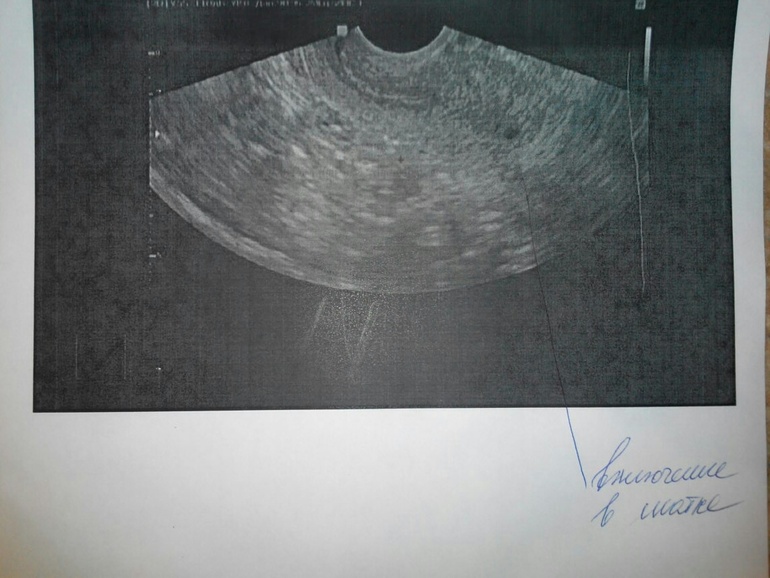

А врач то что говорит, на снимке явно полость какая-то с оболочкой, контур четкий

Вам же врач узи рекомендовал сдать кровь на хгч, будет ясность по поводу меточной/внематочной беременности.